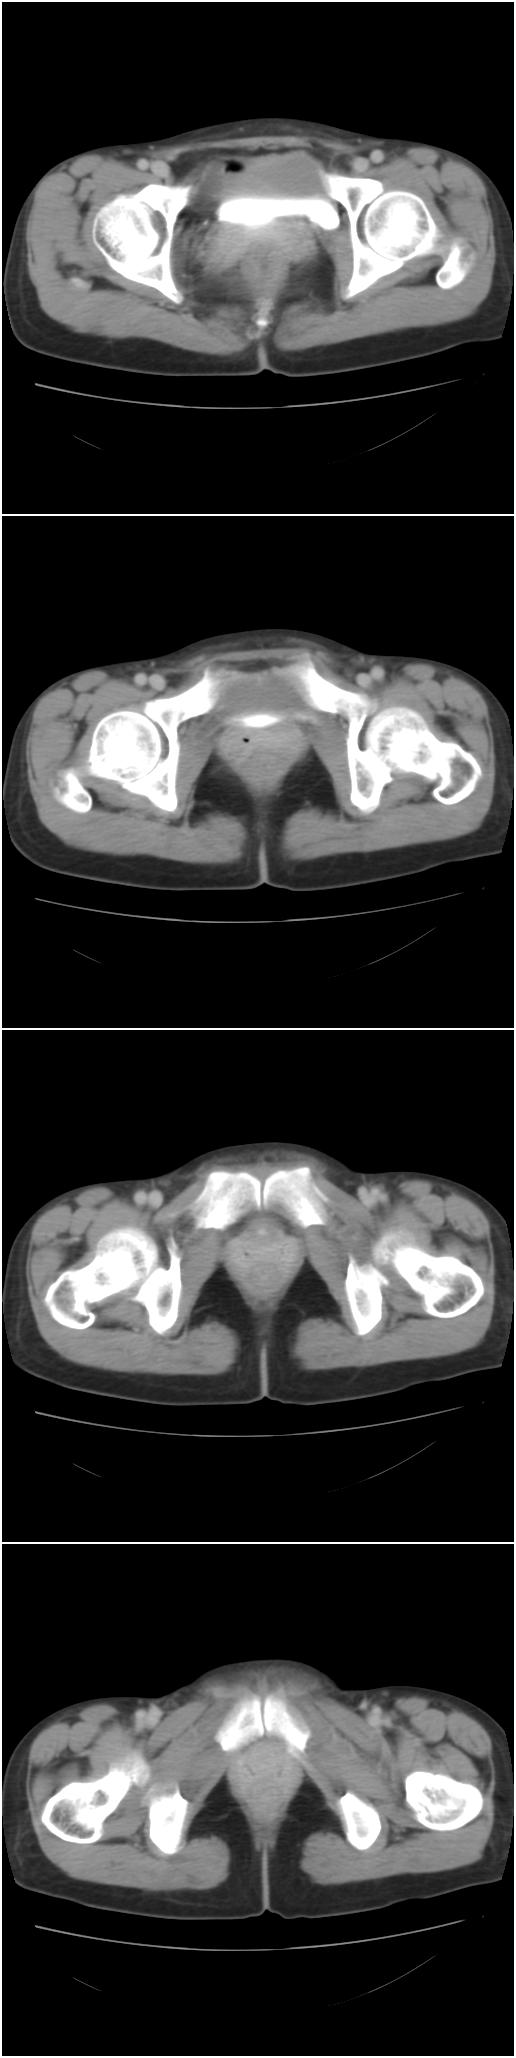

以下是今天的增强片,大家可以看看:

右髂骨见一类圆形略高密度区,似见分层,骨质破坏不明显

考虑良性病变,以动脉瘤样骨囊肿可能性大

右侧髂骨后缘囊状膨胀性骨质改变,无明显骨间隔,周围无明显硬化及骨膜反应,周围软组织无异常,相邻骨组织密度增高,考虑:动脉瘤样骨囊肿可能,要注意与骨巨细胞瘤及转移瘤鉴别。

囊性;密度均;未见分格;骨囊肿

右侧髂骨膨胀性骨质破坏区 囊内密度尚均匀 骨巨细胞瘤可能性大 动脉瘤样骨囊肿不除外 建议mr观察囊内成分明确诊断 左侧附件区包裹性积液

右侧髂后上棘局限性囊状骨质破坏,大部分界清,似见轻度硬化边,内无分格及钙化,病灶上部局部显示模糊。考虑;骨巨细胞瘤可能大,不除外abc。另可见子宫肌瘤术后子宫缺如。